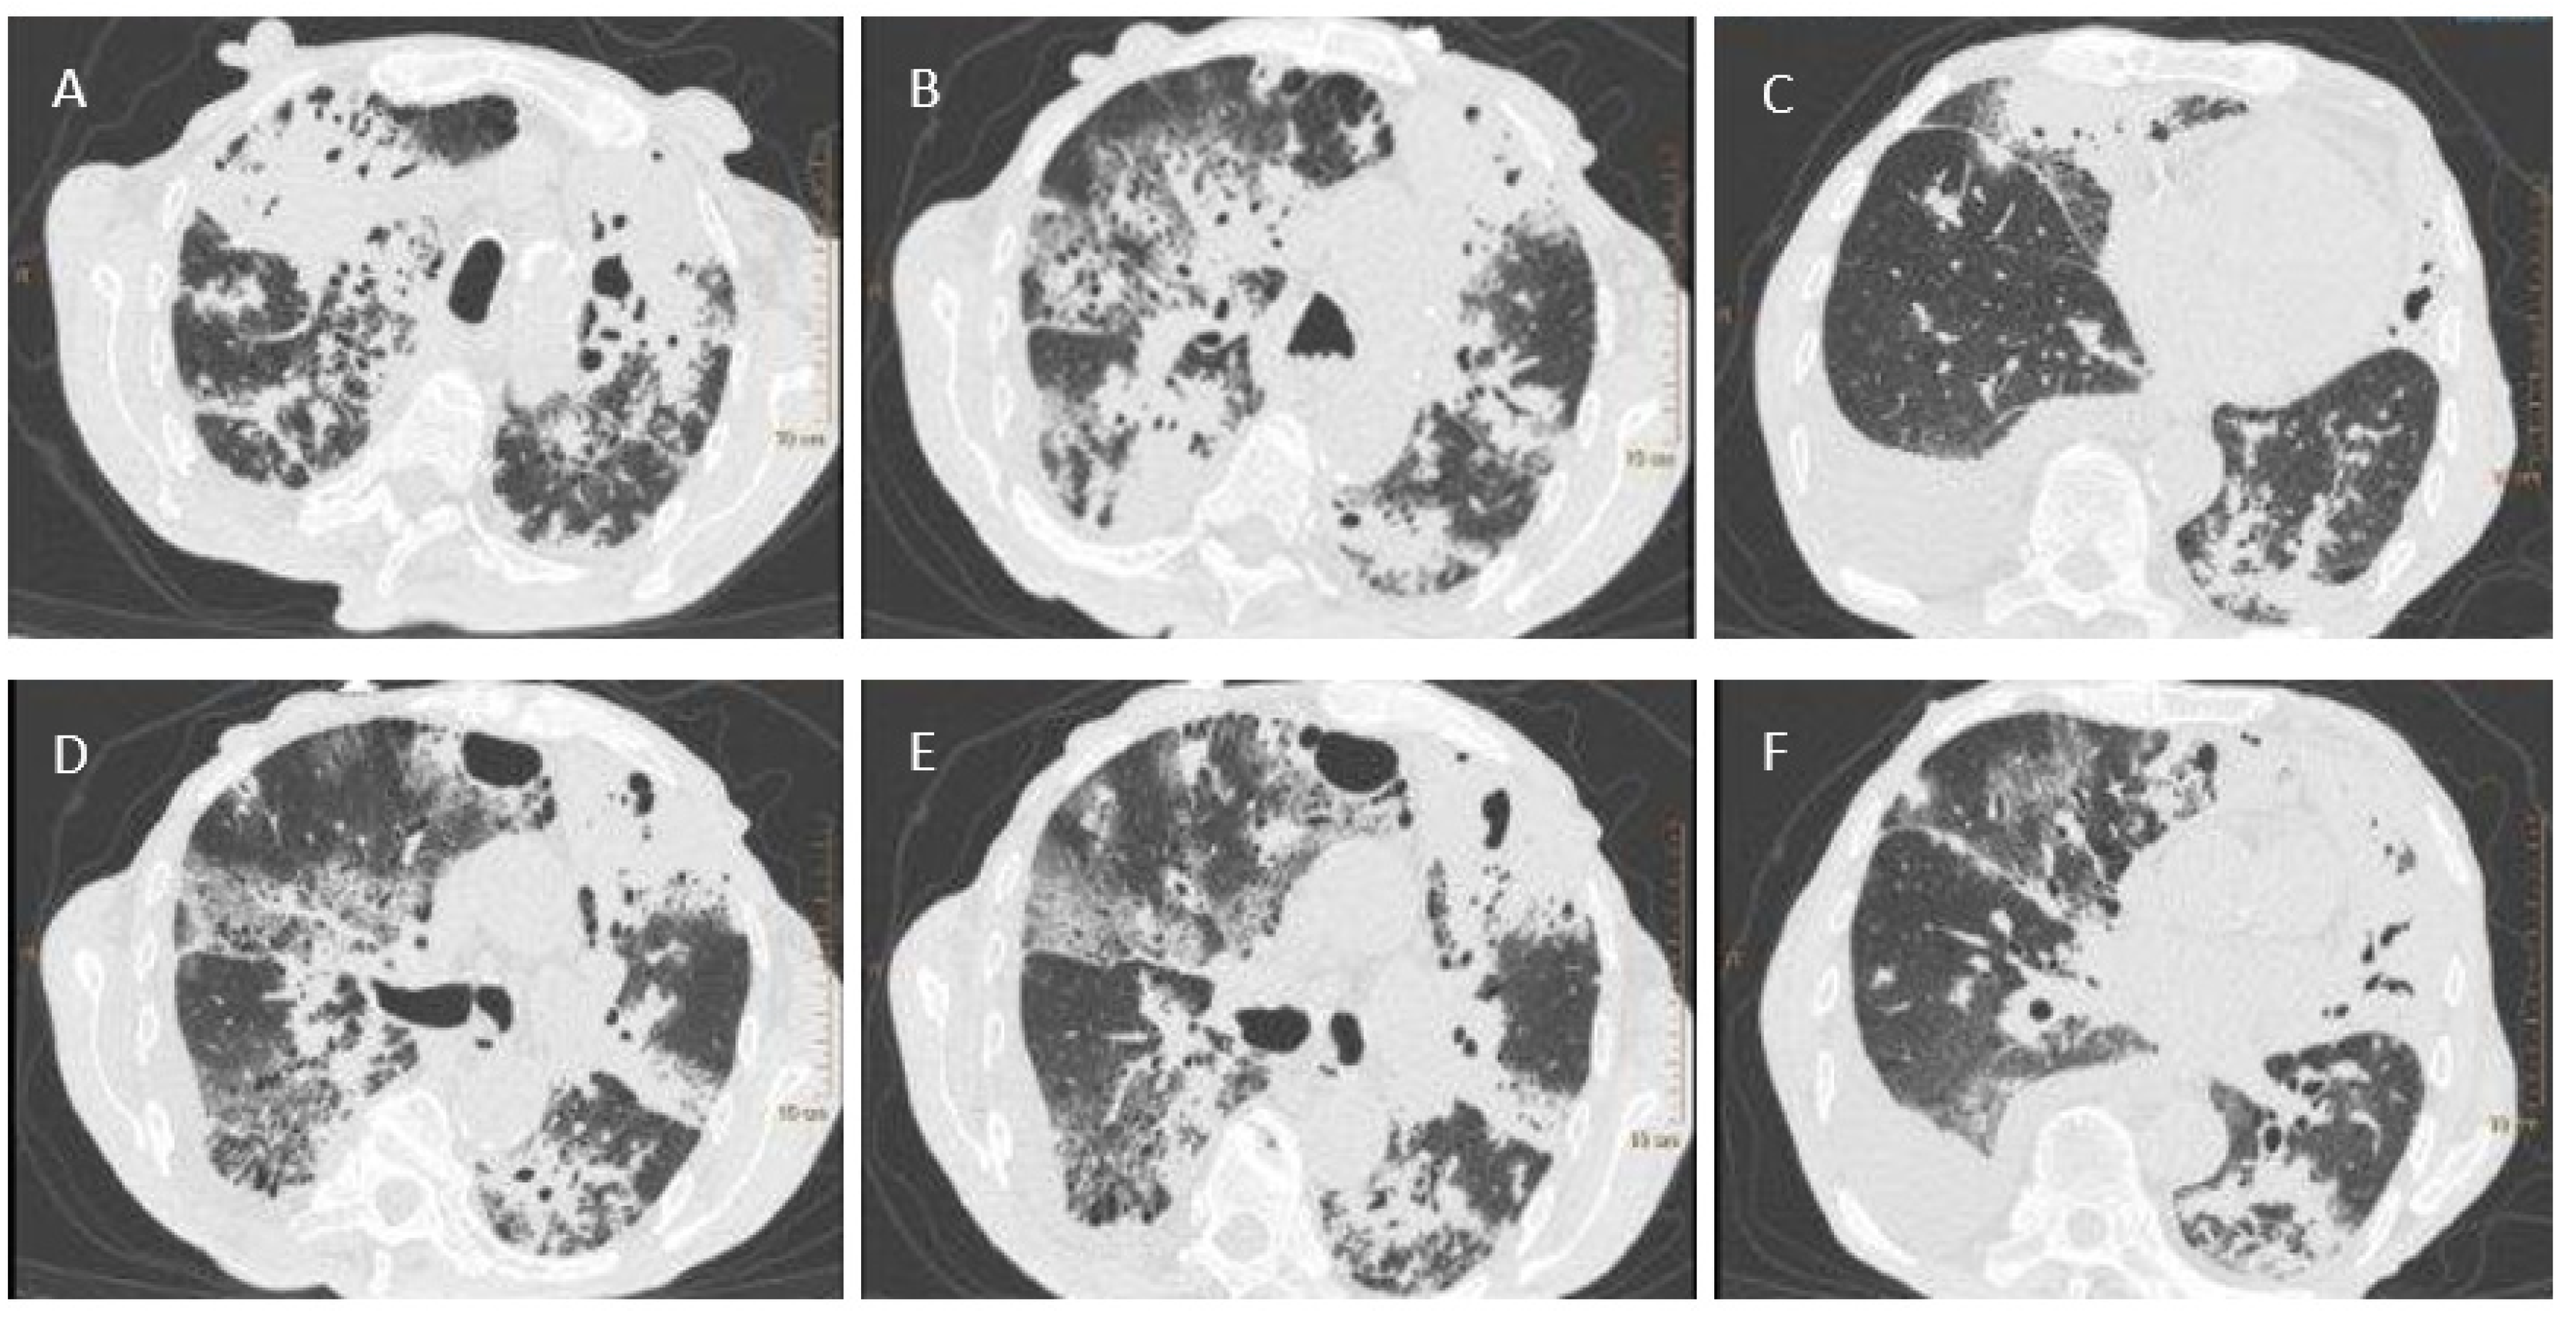

For further TB diagnosis, sputum was sampled from the patient and sent to the NRLT. The analysis of the fluorescent-stained microscopic smear using the Ziehl–Neelsen technique revealed the presence of acid-fast bacilli (AFB+++) (Figure 2A). The GeneXpert assay confirmed the presence of genetic material from MTBC. An identification and drug sensitivity test for the isolated strain confirmed it belonged to the species Mycobacterium tuberculosis and was sensitive to streptomycin (SM), INH, RMP, EMB, and PZA.

An HIV-positive, 64-old patient was treated in 2018–2019 for pulmonary tuberculosis and urogenital tuberculosis, which was confirmed by a positive bacteriological test in NRLT. Back then, assays revealed the presence of mycobacteria in sputum and urine smears (Figure 2B,C). In the genetic assay, Mycobacterium tuberculosis complex (MTBC) DNA was detected in clinical materials, and mycobacterial strains sensitive to SM, INH, RMP, EMB, and PZA were cultured.

Figure 2. Acid-fast bacilli visible after Ziehl–Neelsen staining; (A)—sputum (Patient 1); (B)—urine (Patient 2); (C)—sputum (Patient 2).